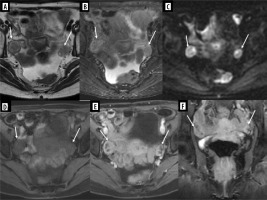

Ultrasound (US) at our institution identified 2 solid lesions with suspected metastatic characteristics alongside the primary foot tumour: one in the right ovary (oval, relatively homogeneous, with medium-high echogenicity, approximately 20 × 16 × 16 mm – Figure 5A) and the other one in the right fifth intercostal space (hypoechoic, with slightly polycyclic outlines, about 14 × 11 × 7 mm). Pelvic MRI corroborated the presence of these findings and additionally detected metastasis in the left gluteus maximus muscle and a suspicious left inguinal lymph node. The ovarian metastasis exhibited peripheral diffusion restriction and contrast enhancement (Figures 5B-F).

Figure 5

Exams of the right ovary metastasis in Patient no. 1. A) Initial ultrasound; axial and sagittal plane. B-F) Pelvic magnetic resonance imaging. B) FSE/T2, axial plane, C) STIR, coronal plane, D) WATER/T1 post-Gd, axial plane, E) DWI, axial plane, F) corresponding ADC map

RMS metastases to the ovary rarely cause symptoms [22]. In our patient, a lesion in the right ovary was incidentally detected during abdominal US before the initiation of treatment. Both US and MR images did not show specific features. However, with the knowledge of the primary tumour in the foot, the nature of the focal lesion in the ovary became evident.

A 15-year-old patient was admitted to our institute for further diagnosis and treatment of a sacral bone tumour. A few days earlier, she was admitted to another centre with shortness of breath, blueness of the fingers, and coldness of the left lower limb. Computed tomography (CT) of the chest, abdomen, and pelvis performed at that time revealed the following: 1) pulmonary embolism with infarction of the lower segments of the left lung; 2) partially sclerotic tumour of the sacrum with aggressive periosteal reactions, extensive periosteal masses with calcifications surrounding the sacrum, infiltrating dorsal and piriform muscles, spreading paraspinally, penetrating the spinal canal through the left intervertebral foramina L2/L3, L3/L3, and L4/L5 and metastatic foci in the L4 and L5 vertebrae; 3) tumour plugs in the vessels – inferior vena cava to the level of the right atrium, common iliac veins, internal iliac veins, left external iliac vein, smaller pelvic veins, including uterine venous plexus, and massive collateral circulation with tumour plugs (Figure 6).

Figure 6

Exams of Patient no. 2 with tumour plugs in the vessels. A, B) Computed tomography (CT) shows partial sclerotic tumour plugs in many vessels, including uterine venous plexus. A) Coronal plane, B) axial plane. C) CT scan shows chondrosarcoma of the sacrum; axial plane. D) MRI study; STIR, coronal plane